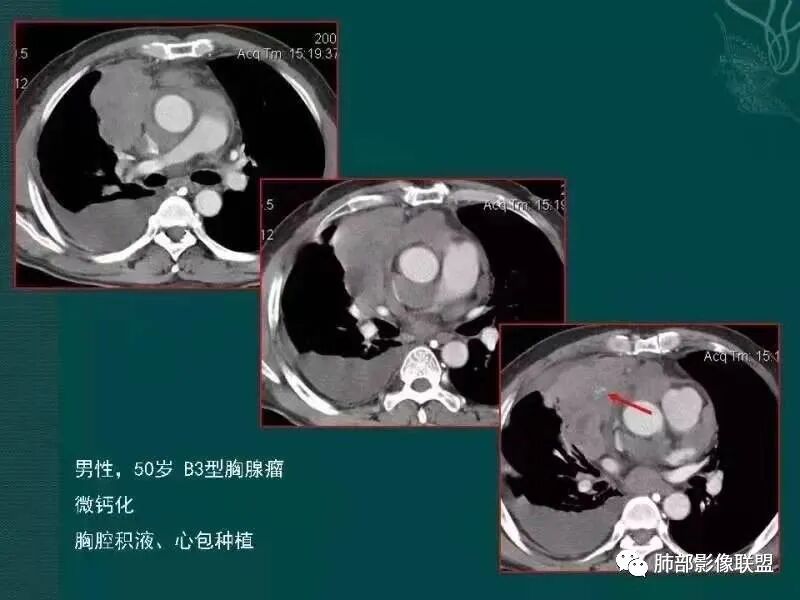

病史,老年女性,检查发现前上纵隔占位。

前上纵隔偏左侧实性病灶,边界清楚,边缘彭隆,浅分叶,内部密度均匀,未见钙化、脂肪密度,周围脂肪间隙清晰。

包膜完整,纤维分隔,结节感明显

平扫密度较均匀,增强渐进性不均匀强化,内见低密度纤维分隔。未见肿大淋巴结。未见胸腔积液。

肿块边界清楚,低密度纤维间隔,未见侵犯转移及增大淋巴结,多见于胸腺瘤AB型